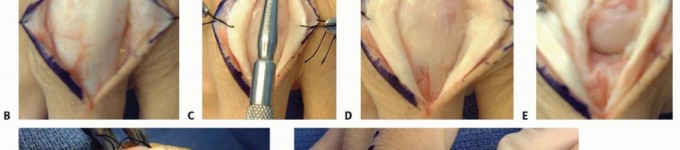

The surgical release of an MCP extension contracture is typically approached dorsally. A longitudinal incision is made directly over the metacarpal shaft, extending distally over the proximal phalanx. Alternatively, a dorsal curvilinear or lazy-S incision can be utilized to prevent a linear scar contracture. Meticulous subcutaneous dissection is performed to identify and retract the delicate dorsal sensory branches of the radial or ulnar nerves. The extensor mechanism is exposed.

The EDC tendon is frequently adherent to the underlying capsule. The sagittal bands are identified on both the radial and ulnar aspects of the EDC. The extensor mechanism is longitudinally split, or the sagittal bands are carefully elevated from the underlying capsule to allow retraction of the EDC tendon laterally. This exposes the thickened, fibrotic dorsal capsule. A transverse or elliptical excision of the dorsal capsule is performed. Often, this initial step yields minimal improvement in flexion, indicating that the primary pathology lies within the collateral ligaments.

The proper collateral ligaments are identified originating from the metacarpal head tubercles. In a severe extension contracture, these ligaments are shortened, thickened, and densely scarred to the lateral condyles. Using a #15 blade, the proper collateral ligaments are sharply released from their proximal attachments on the metacarpal head or excised entirely. The accessory collateral ligaments, which fan out to the volar plate, are ideally preserved to maintain some degree of lateral stability, though they too must be released if they remain a tether to flexion. Following collateral ligament release, gentle, sustained passive flexion is applied. If resistance persists, a freer elevator is passed volarly to lyse adhesions between the volar plate and the metacarpal head. If the joint remains incongruous or tends to subluxate dorsally upon flexion, temporary transarticular Kirschner wire (K-wire) fixation in 70 degrees of flexion for 7-10 days may be necessary, though immediate mobilization is vastly preferred.

Proximal Interphalangeal Joint Release Technique

The release of a PIP flexion contracture is arguably more demanding. A midaxial incision (either radial or ulnar, depending on concurrent pathology) or a volar Bruner zig-zag incision is employed. The midaxial approach provides excellent exposure of the collateral ligaments and lateral aspect of the volar plate while remaining dorsal to the neurovascular bundle. The neurovascular bundle is identified, mobilized, and protected throughout the procedure.

Following the principles of Curtis, the release is performed sequentially. First, the lateral bands of the extensor mechanism are mobilized, and any adhesions to the proximal phalanx are lysed. Second, the transverse retinacular ligament is divided. Third, the proper collateral ligaments are assessed. If they are contracted and preventing extension, they are completely excised from their origin on the proximal phalanx to their insertion on the middle phalanx. Excision is preferred over simple transection to prevent the immediate reformation of scar tissue bridging the gap.

The critical step is the management of the volar plate. The accessory collateral ligaments are divided to allow access to the proximal aspect of the volar plate. The check-rein ligaments—the dense, fibrotic bands tethering the volar plate to the periosteum of the proximal phalanx—are identified and radically excised. The proximal margin of the volar plate must be completely freed, allowing it to glide distally as the joint is extended. If full extension is still not achieved, a flexor tenolysis within the A2 or A3 pulley region may be required. Once full, passive extension is obtained, the tourniquet is deflated to ensure the digital artery has not been placed under undue tension, which could precipitate vasospasm and digital ischemia.